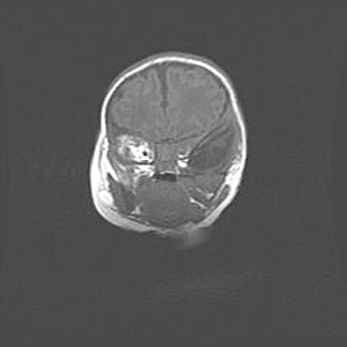

Сообщающаяся гидроцефалия. Кистозная энцефаломаляция головного мозга.

Возраст: 3 месяца 4 дня

Вес: 3100 г

Пол: женский

Окружность головы: 34 см

Срок гестации: 31 неделя

Кистозная энцефаломаляция головного мозга - одна из форм поражения головного мозга в детском возрасте. Характеризуется возникновением множественных и распространённых кист в коре, белом веществе и подкорковых образованиях головного мозга у плодов, новорождённых и детей раннего возраста. Развитие кистозной энцефаломаляции связано с внутриутробной асфиксией и гипотонией, родовой травмой, тромбозом синусов, пороками развития сосудов, инфекциями, сепсисом и другими причинами. Наиболее значимые инфекционные агенты: вирусы простого герпеса, цитомегалии, краснухи, токсоплазмы, энтеробактерии, золотистый стафилококк и другие.